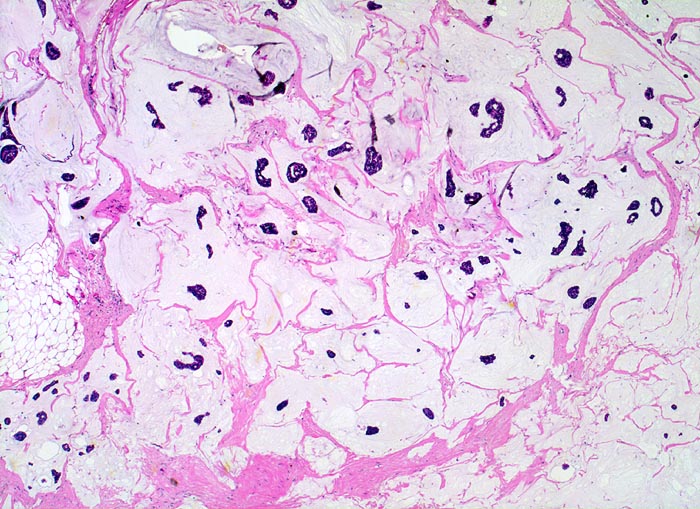

PathoPic ID 3866 - Muzinöses Mammakarzinom (Kolloidkarzinom)

Muzinöses Mammakarzinom (Kolloidkarzinom)

maligner Tumor

Mamma

Kleine kompakte Tumorzellinseln schwimmen in extrazellulären Schleimseen.

Histologie

25